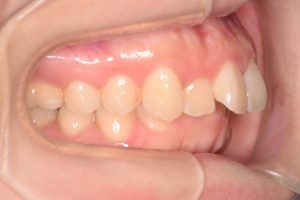

左側

0000000010

0000000138